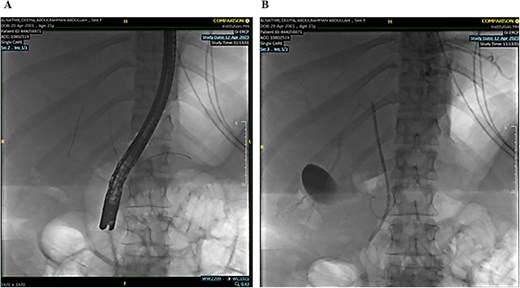

The remaining hepatic parenchyma had homogenous enhancement and smooth outlines. As shown in Fig. 4, the Endoscopic retrograde cholangiopancreatography (ERCP) was performed using double-guided wire and successfully resulted in bile duct cannulation.

Endoscopic retrograde cholangiopancreatography (ERCP): Demonstrating the cannulation procedure and the placement of the cannula.